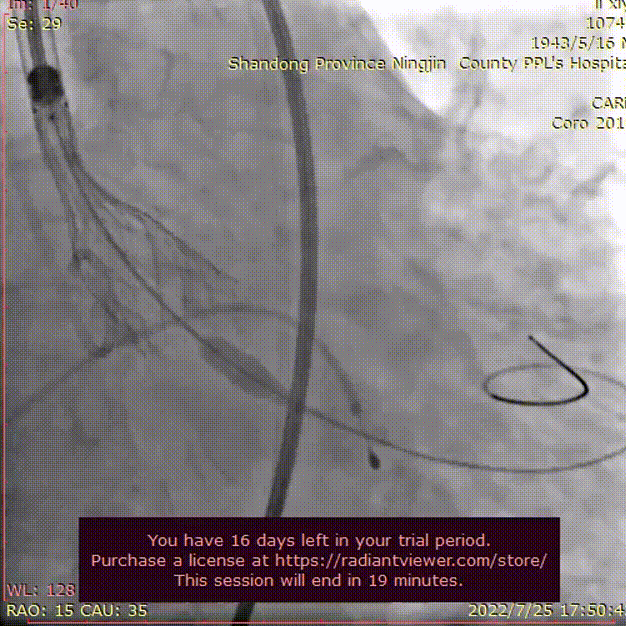

在Ecmo辅助下,行主动脉根部造影,猪尾确定选择最佳释放体位,观察瓣叶活动,确认是否合并反流,选择合适体位跨瓣。

主动脉根部根部造影

术者团队用25mm球囊预扩,结合瓣环及球囊预扩情况,预装AV29型号瓣膜。患者横位心,在抓捕器辅助下输送器过弓。

球囊预扩

造影评估

术者结合DSA影像,多角度观察瓣膜情况,在瓣膜释放至工作位造影。

初始定位释放

工作位

无明显返流,瓣膜形态佳,工作稳定。

工作位评估

完全释放